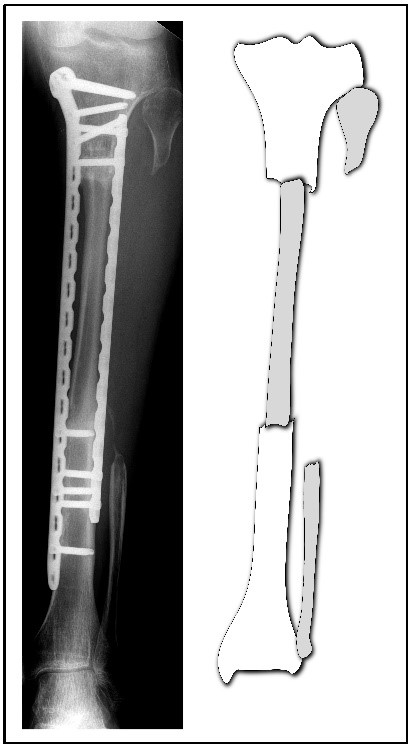

Abb. links: Bei dieser Rekonstruktion wurde ein Tumor aus der Tibia (Schienbein) entfernt. Das fehlende Stück der Tibia wurde durch ein gleich langes Stück Fibula (Wadenbein) überbrückt. Durch die Fixierung mittels zweier Platten kann der neue Knochen zusammenheilen und das Bein ist wieder belastbar.

Abb. rechts: Schemazeichnung mit Tibia (weiß) und Fibula (grau)